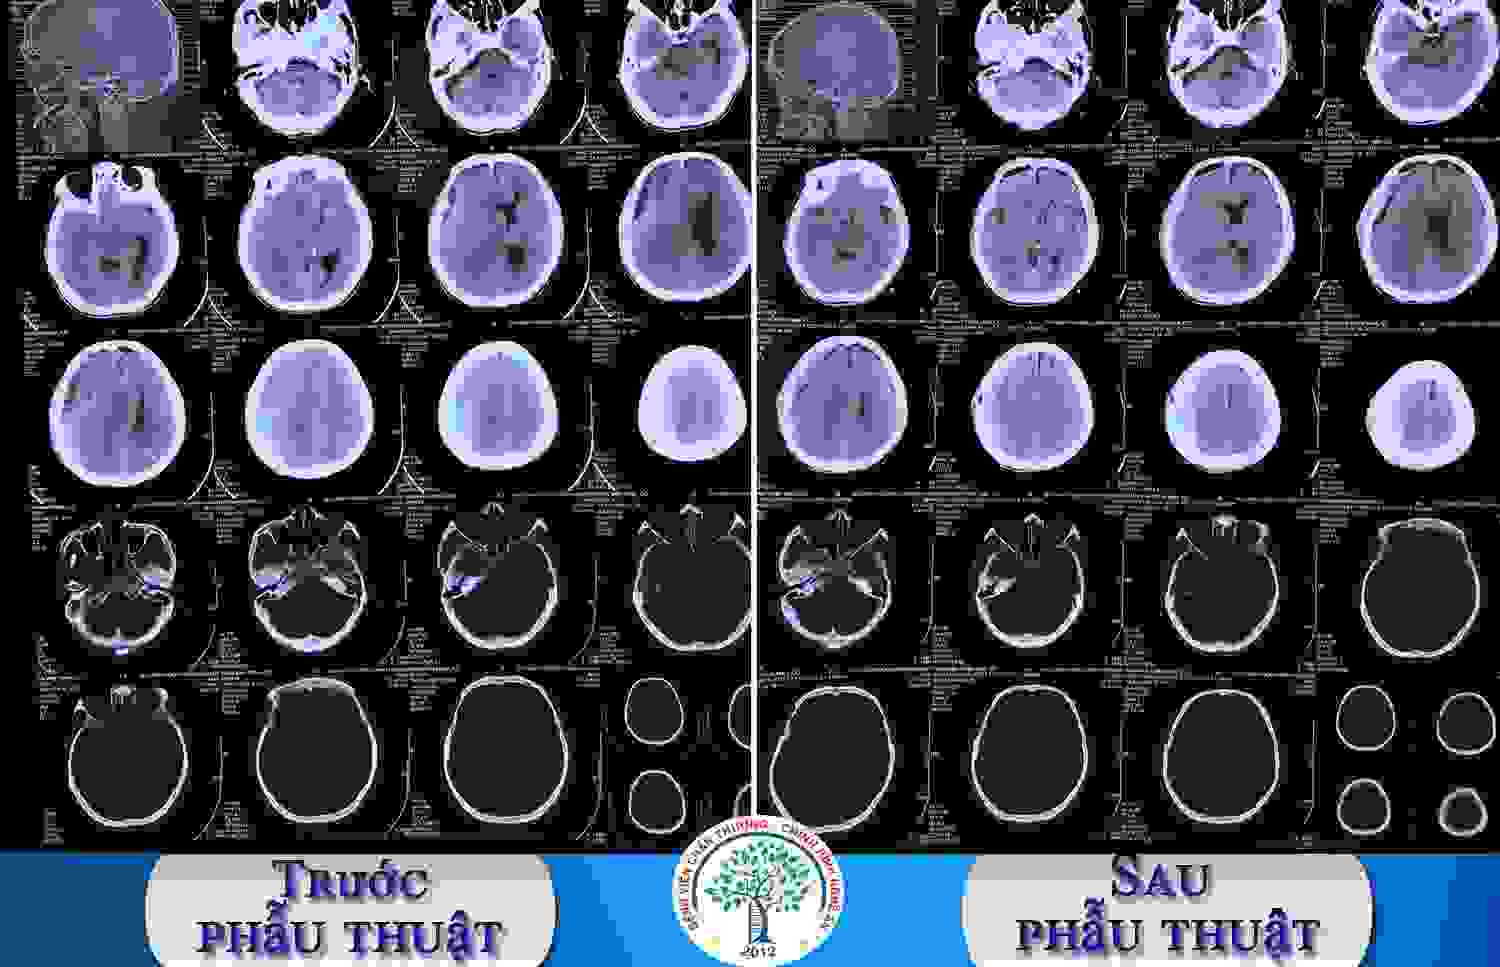

Tụ máu dưới màng cứng mạn tính - Nguy hiểm tiềm tàng

Bệnh nhân T.V.T., 56 tuổi, tại Thanh Chương, Nghệ An có tiền sử Tâm thần phân liệt đang điều trị với Olanzapine, xuất hiện tình trạng đau đầu đã lâu. Cách vào viện 24 giờ, bệnh nhân bị ngã va đập đầu vào nền nhà. Sau ngã bệnh nhân tỉnh, đau đầu, sau đó xuất hiện tình trạng buồn nôn và nôn. Bệnh nhân được chuyển vào cấp cứu tại Bệnh viện Chấn thương Chỉnh hình Nghệ An.